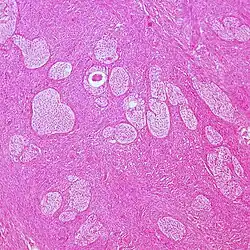

| Surface epithelial-stromal tumor | Serous tumor | 25% | 18.5% | Benign serous tumors of the right ovarian cyst are thinwalled unilocular cysts that are lined by ciliated pseudostratified cuboidal or columnar epithelium.[9] |

| Mucinous tumor | 15% | 8.8% | Benign mucinous tumors of the ovary consist of simple, nonstratified columnar epithelium with basally-located hyperchromatic nuclei and resemble gastric foveolar epithelium.[9] |